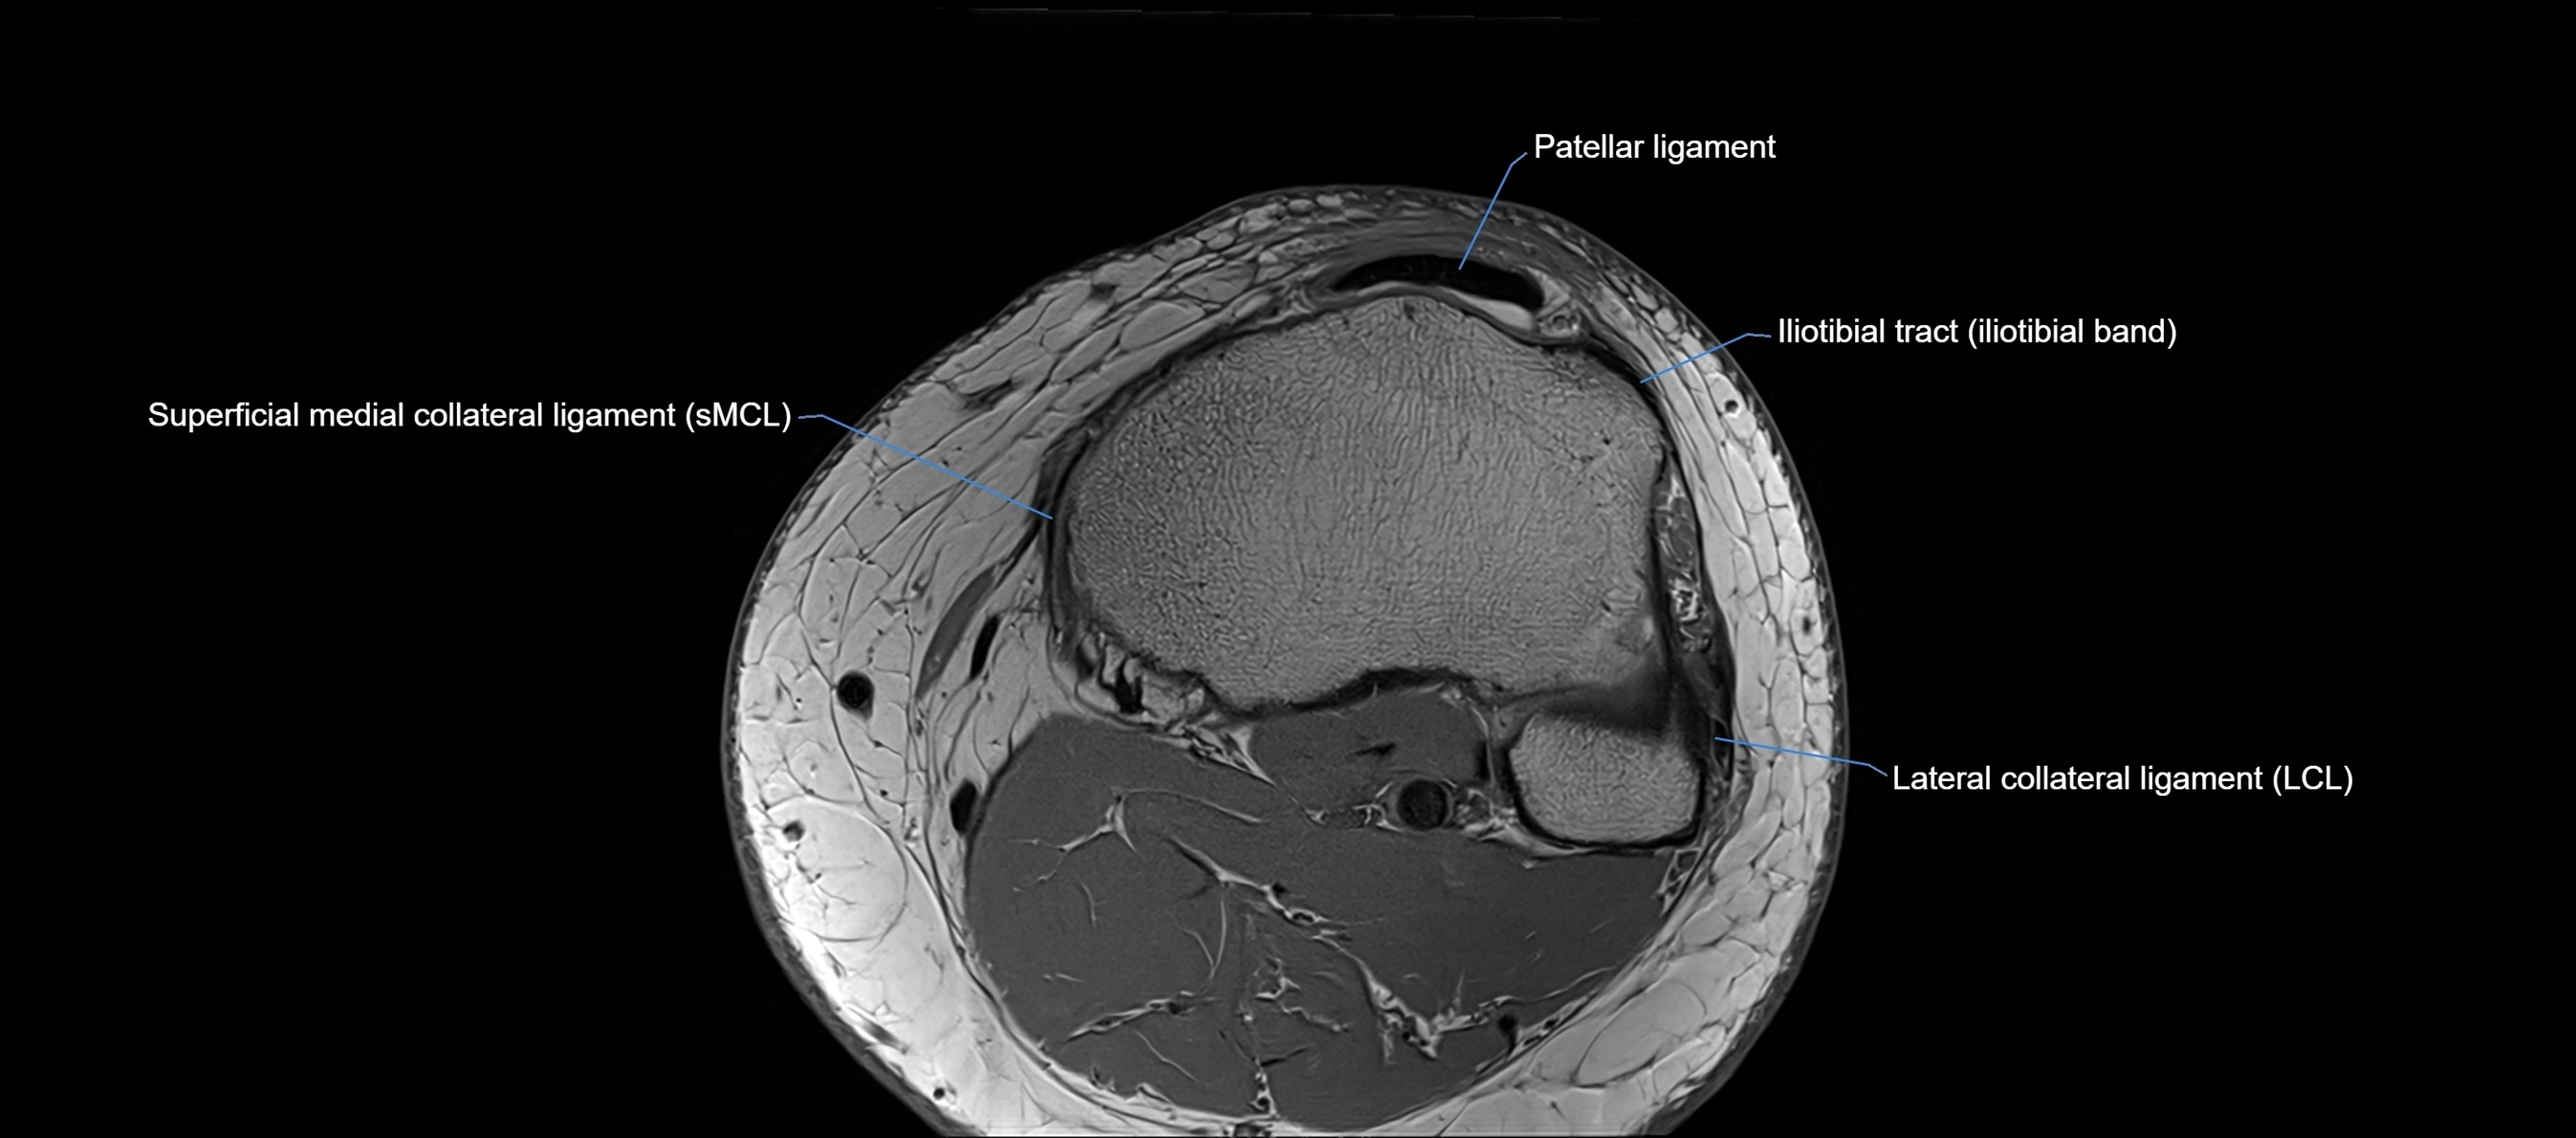

MRI images

image